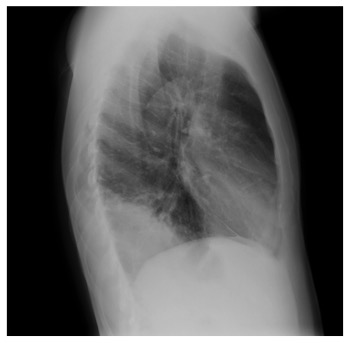

Paciente de 65 años al que se le realiza con dolor en hemitórax derecho más frebrícula:

Se procede a realizar un TC abdominal:

Elevación del hemidiafragma derecho una lesión quistíca de gran tamaño en segmento VII que continua con el segmento VI. Que pierde plano de clivaje con espacio pararrenal anterior

Estamos presenciando el lugar de afectación más frecuente de la Hidatidosis, el Hígado, concretamente sería el lóbulo hepático derecho, el cual se ha abierto al hemitórax derecho por una rotura directa.

En el examen clínico debe valorarse el estado general y el estado nutricional del paciente, los que a menudo se hallan afectados. La hepatomegalia se observa como manifestación de quistes localizados en los segmentos inferiores o quistes intrahepáticos que rechazan el hígado hacia abajo o es secundaria a una hipertrofia compensadora. La semiología de la base del hemitorax derecho puede llegar a dar signos en caso de una elevación diafragmática en quistes de la región superior de hígado y tendrá hallazgos manifiestos de las complicaciones toráxicas de la hidatidosis hepática.